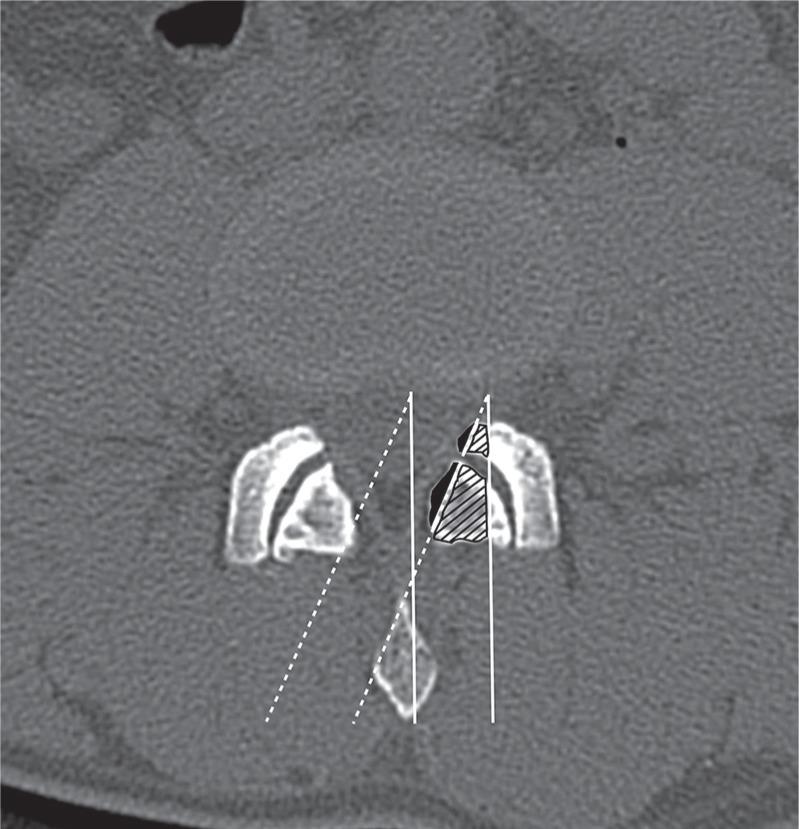

The purpose of this study was to determine the feasibility and efficacy of bilateral decompression procedure via microscopic tubular crossing laminotomy (MTCL) for treating lumbar spinal stenosis (LSS). Seventeen patients with LSS underwent bilateral decompression via an MTCL procedure in which tubular retractor was placed. The mean age was 72 (range 59-84) years and there were 10 men and 7 women. All patients underwent pre- and postoperative dynamic lumbar x-ray, magnetic resonance (MR) image, and computed tomography. To verify the efficacy of this technique, pre- and postoperative cross-sectional area (CSA) of thecal sac, facet resection, and fatty infiltration (FI) of multifidus were measured. Clinical results were evaluated using Oswestry Disability Index (ODI), back and leg visual analog scale (VAS). The mean follow-up period was 17.5 months (range 12.1-21.2). 70.5% of MTCL was performed at the level of L4-5 and one case of dural violation (5.8%) was noted at the level of L5-S1. The mean preoperative CSA was 70.5 mm(2) (range 25.1-87.6) and it increased to 198.8 mm(2) (range 177.3-219.2) postoperatively (p = 0.00). The mean facet resection rate was 18.4% (range 9.9-26.9) and no radiological instability was noted postoperatively. MR image showed no increase in FI of the multifidus after 12 months of follow-up (p = 0.53). Preoperative clinical symptoms improved significantly at postoperative 6 months and 12 months of follow-up. These results indicate that an MTCL with use of tubular retractor system can be an effective procedure to achieve neural decompression for the treatment of LSS and it may be beneficial in preserving both facet joint and multifidus muscle.

本研究旨在确定经显微管状交叉椎板切开术(MTCL)行双侧减压治疗腰椎管狭窄症(LSS)的可行性和疗效。17例LSS患者接受了经MTCL双侧减压手术,术中放置了管状牵开器。平均年龄为72岁(范围59 - 84岁),男性10例,女性7例。所有患者均接受了术前和术后动态腰椎X线、磁共振(MR)成像及计算机断层扫描。为验证该技术的疗效,测量了术前和术后硬脊膜囊的横截面积(CSA)、关节突切除情况以及多裂肌的脂肪浸润(FI)。使用Oswestry功能障碍指数(ODI)、腰背部和腿部视觉模拟量表(VAS)评估临床结果。平均随访期为17.5个月(范围12.1 - 21.2个月)。70.5%的MTCL手术在L4 - 5节段进行,在L5 - S1节段有1例出现硬脊膜损伤(5.8%)。术前平均CSA为70.5 mm²(范围25.1 - 87.6),术后增加至198.8 mm²(范围177.3 - 219.2)(p = 0.00)。平均关节突切除率为18.4%(范围9.9 - 26.9),术后未发现影像学不稳定。随访12个月后,MR图像显示多裂肌的FI无增加(p = 0.53)。术前临床症状在术后6个月和12个月的随访中显著改善。这些结果表明,使用管状牵开器系统的MTCL可能是一种有效的神经减压手术,可用于治疗LSS,并且可能有助于保留关节突关节和多裂肌。